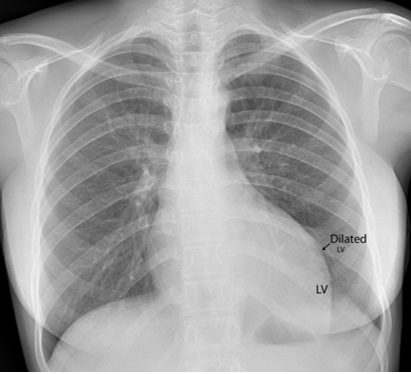

A 17-year-old female was brought to the emergency room with a history of sudden onset of breathlessness. Her pulse rate was 87 bpm and blood pressure 110/60 mmHg. She had a history of rheumatic fever during childhood, an episode of febrile illness for 10 days and taken antibiotic treatment recently. Blood chemistry revealed normal and blood cultures were negative. ECG revealed normal as shown in Figure 1 and X-ray chest revealed dilated LV (left ventricle) as in Figure 2. Physical examination revealed grade 3/6 early diastolic murmur over left mid sternal border, basal crackles over lung fields and no peripheral signs of wide pulse pressure. Transthoracic echocardiography revealed vegetations on anterior and posterior leaflets of aortic valve as in Figure 3 and Figure 4, with a “kissing-type “as in Figures 5, 6 and 8. The aortic valve was bicuspid with an attached vegetation as in Figure 9 and it was severely regurgitant as in Figure 10 and Figure 11. The left ventricle is dilated as in Figure 12 with moderate LV dysfunction as in Figure 13. The thoracic aorta was prominent as in Figure 14 with a ‘holodiastolic flow reversal’ as in Figure 15. The patient was treated with digoxin (0.25 mg, half daily), diuretics (Injection. Furosemide 20 mg IV twice daily), ACE inhibitors (tablet. Enalapril 2.5 mg twice daily) along with 2 weeks course of intravenous (IV) cefotaxime (1g) and amickacin (500mg) twice daily and advised aortic valve replacement at the earliest with lifelong penicillin prophylaxis and continuation of antibiotics for 6 weeks since the vegetations remain stable after 2 weeks of treatment, but without any embolic episodes.

Figure 2: X-ray chest PA (postero-anterior) view showing the dilated left ventricle due to acute severe aortic regurgitation [6] in a 17-year old female.